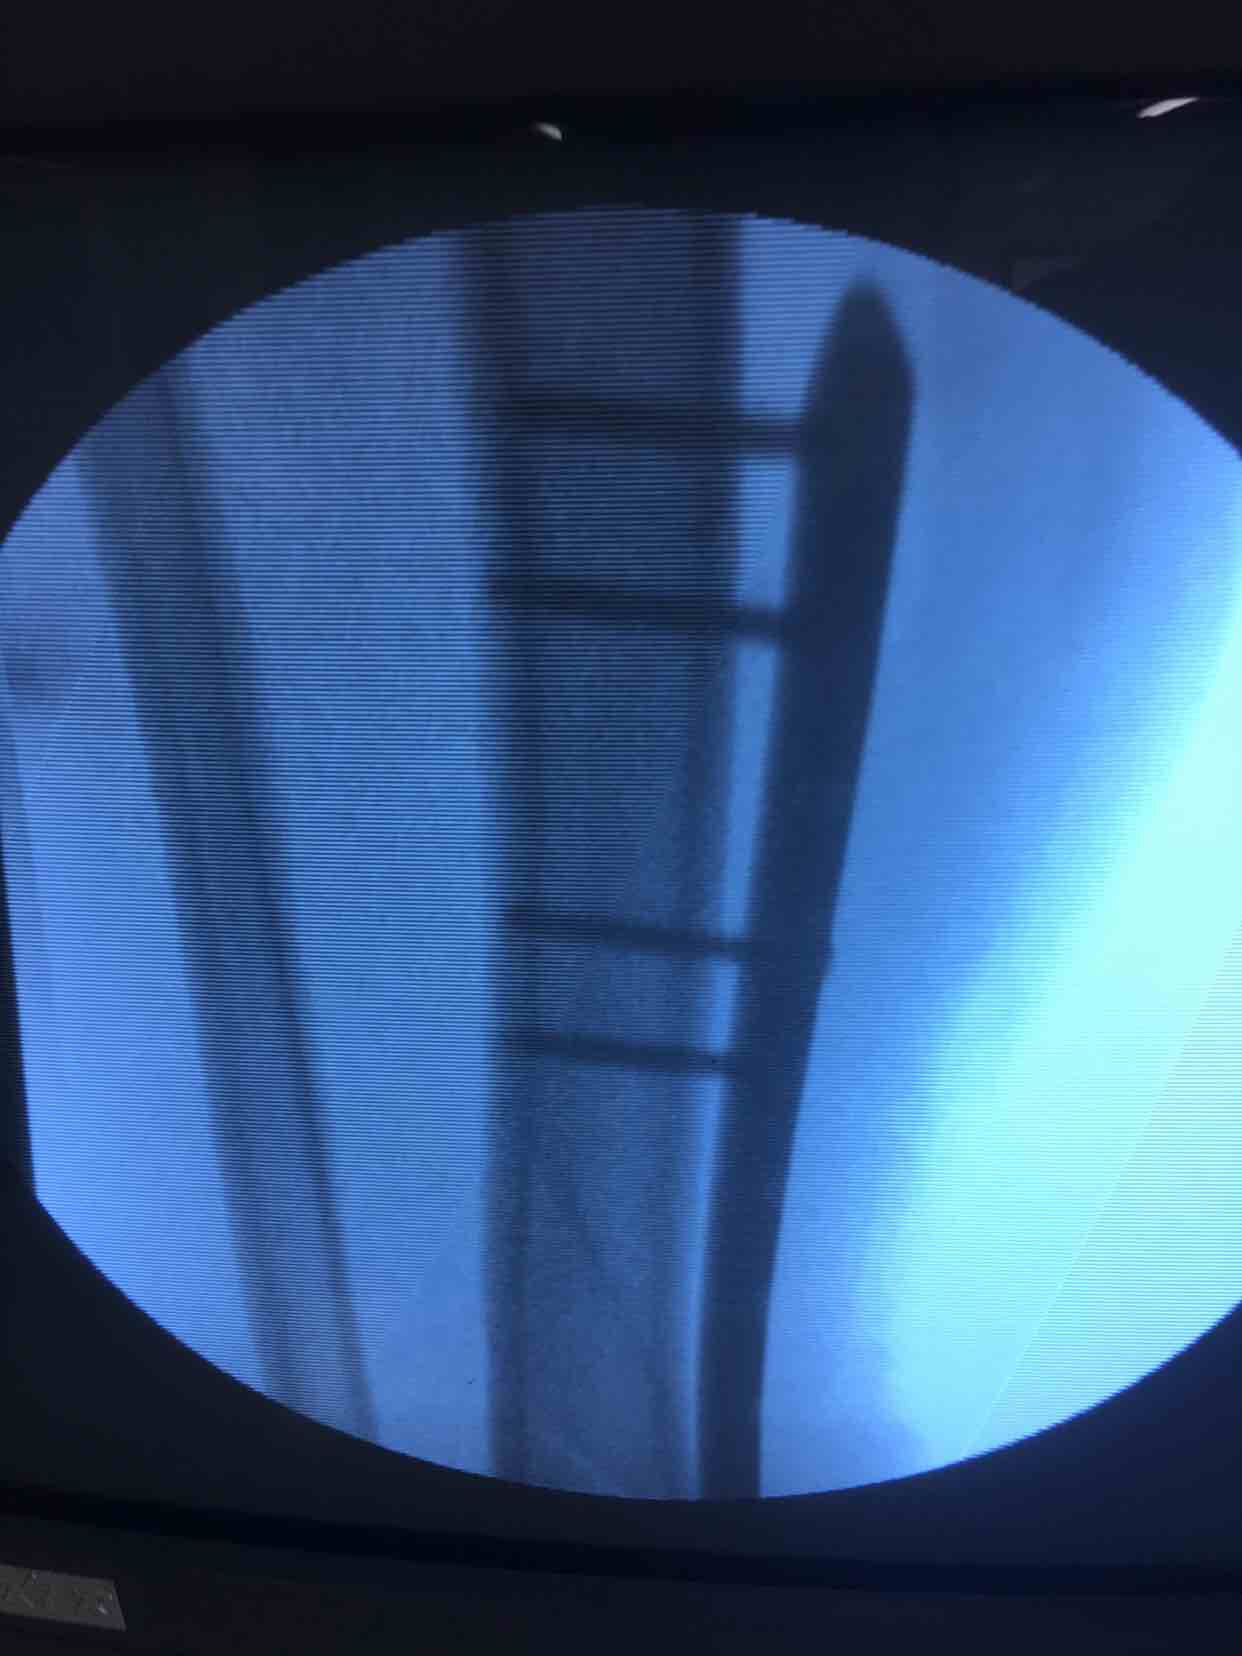

在腰麻下行切开复位内固定术,术后抗炎,消肿等处理。

- 高兵回复导火索:手术方式选择决定术后愈合情况,微创最大优势就是软组织保护,骨折早日愈合。

术后半年复查